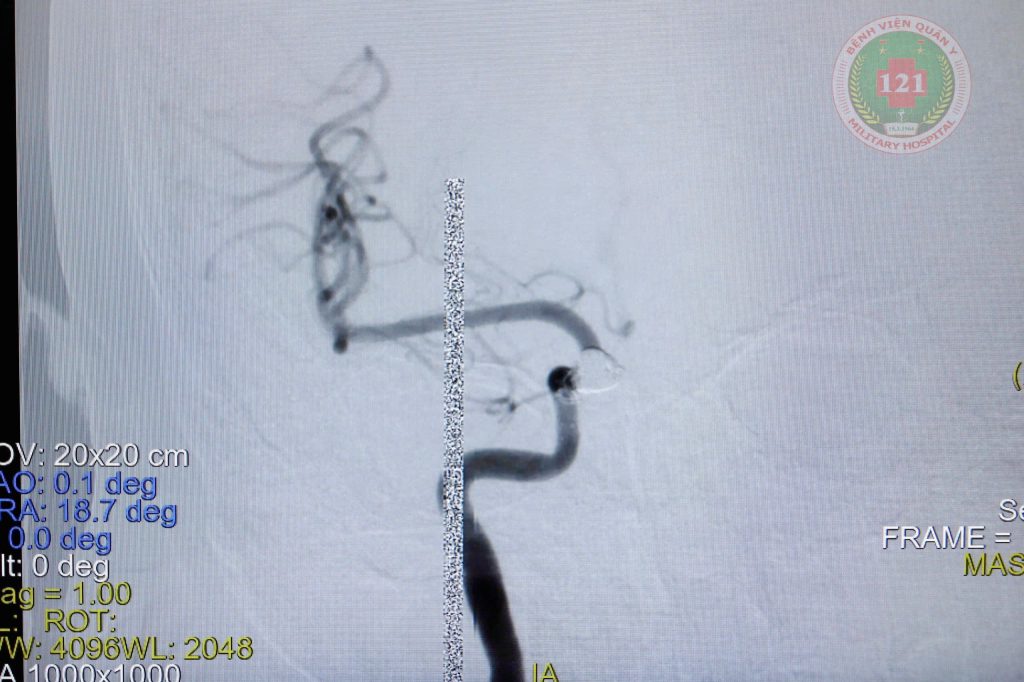

Thông động tĩnh mạch xoang hang trước khi thả coil và sau khi thả coil |